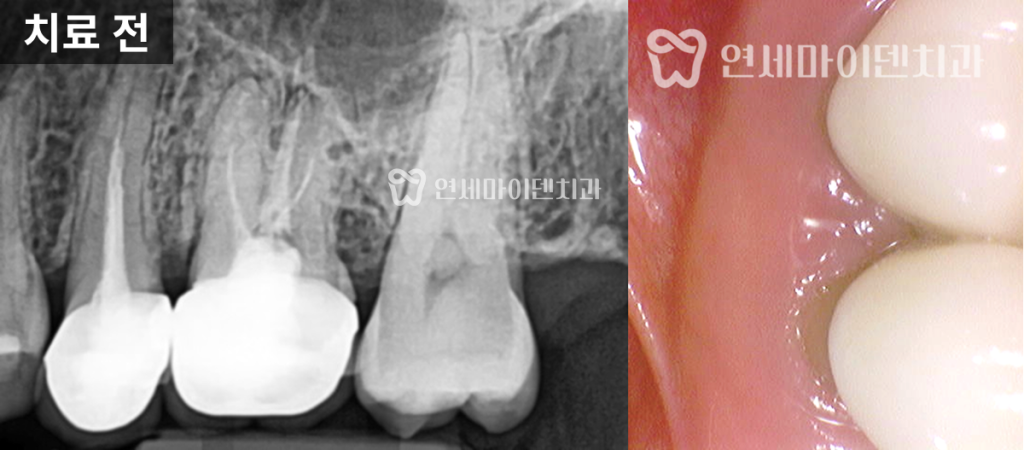

26번 치아 — 발치 즉시 임플란트

그러나 바로 뒤쪽의 #26번 치아는 상황이 달랐습니다.

보철물을 제거하자 내부에서 출혈이 계속되어 CT를 재확인했더니

구개측 뿌리(perforation)가 뚫린 상태였습니다.

염증으로 인해 주변 뼈 손실이 심했고,

이미 MTA(특수 치근 수복재)를 적용하기엔

시기를 놓친 상태였습니다.